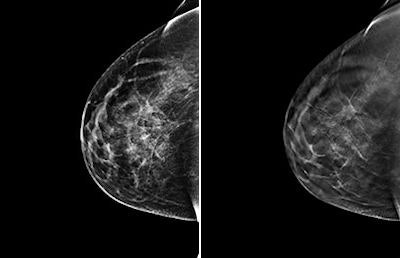

CHICAGO - Adding digital breast tomosynthesis (DBT) to full-field digital mammography (FFDM) improves cancer detection in women with dense breast tissue by 30% versus mammography alone, according to research presented on Tuesday at the RSNA 2014 meeting.

Mammography loses sensitivity in women with dense breast tissue, and other modalities such as breast MR and ultrasound are used to find cancers that mammography misses in this population, noted presenter Dr. Per Skaane, PhD, from Oslo University Hospital in Norway. But MR and ultrasound also have higher false-positive rates than tomosynthesis -- which can result in unnecessary follow-up tests and biopsies.

"Our research shows that tomosynthesis has the potential to significantly increase the cancer detection rate in mammography screening of women with breast density BI-RADS measurements of 2 through 4 -- minimal density to extremely dense," he said. "And it would be much easier to implement in organized screening programs than MRI or ultrasound."

The combination of FFDM and tomosynthesis had a cancer detection rate of 8.1 per 1,000 women, a 30% relative increase compared with FFDM alone, which had a rate of 6.1 per 1,000 women, the researchers found. In addition, the combination exam identified more cancers in denser tissue (BI-RADS 3 and 4) versus digital mammography alone: 80% versus 59%, respectively.

In fact, the combination of FFDM and tomosynthesis improved the cancer detection rate in women with a BI-RADS density measurement of 2, or minimal density, from 68% to 84% -- which could have interesting ramifications for clinical practice, according to Skaane.

"Ninety percent of women fall into the BI-RADS density categories of 2, 3, and 4, which means 90% benefit from tomosynthesis," he said. "So the practical implication of our study is that tomosynthesis should be the standard for breast cancer screening."